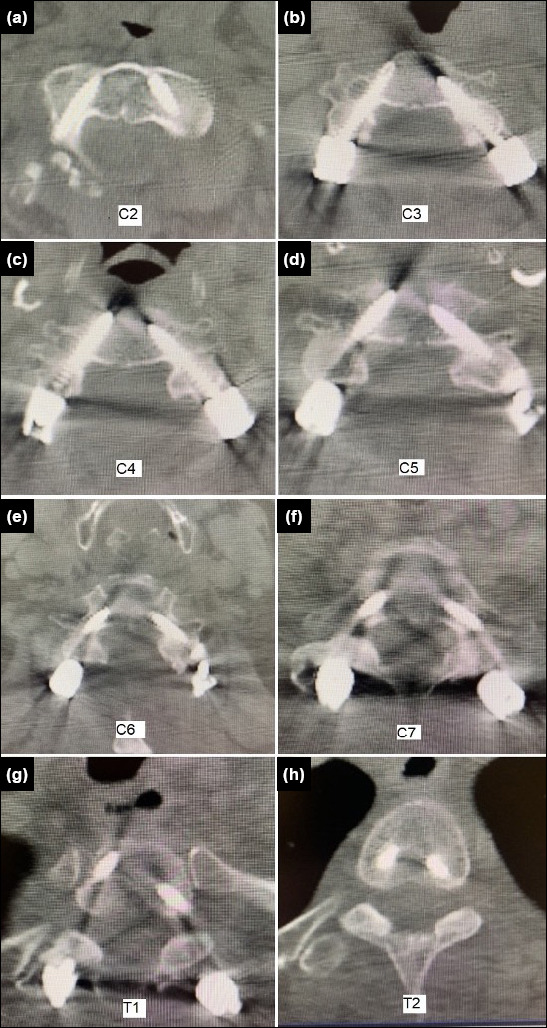

Methods: We retrospectively analyzed patients who underwent cervical subaxial pedicle screw placement between 2017 and 2024. A freehand surgical technique was employed, using a mini-laminotomy approach to ensure safe screw placement. During the procedure, the medial, superior, and inferior borders of the pedicle were palpated.

Results: A total of 70 cases were analyzed retrospectively. Fifty patients were male, and 20 were female. The patients ranged in age from 20 to 89 years (median age: 64 years). Fifty-seven patients (81.5%) had cervical stenosis as the surgical indication. Of the remaining cases, 11 patients had fractures and two had tumors. Among the 468 pedicle screws placed, 434 were graded as 0-1. The correct placement rate was 92.7%. Thirty-four screws were malpositioned (grade 2-3), representing a rate of 7.3%.

Conclusion: In our case series, the accuracy of cervical subaxial pedicle screw placement was high. We believe that achieving this level of accuracy requires a strong understanding of anatomy, three-dimensional spatial awareness, and surgical experience.